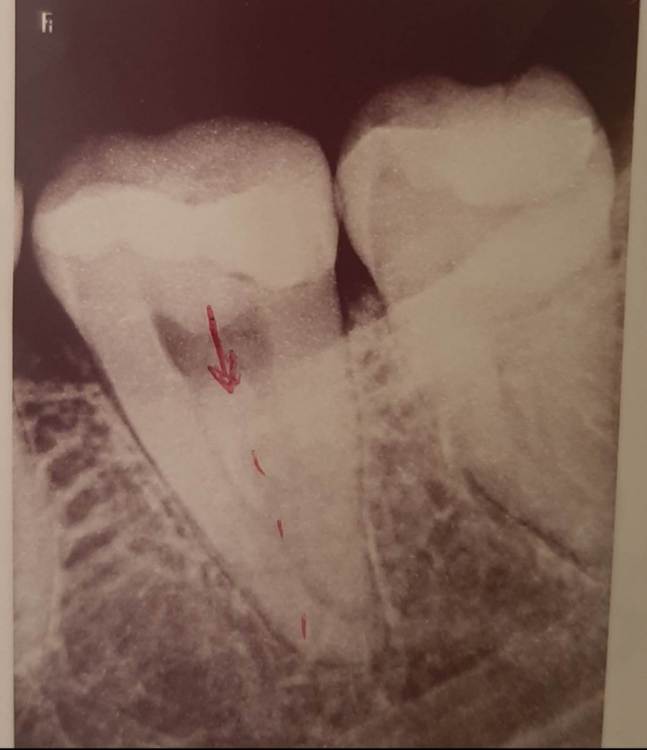

Лана-Лана Опубликовано 6 декабря, 2021 Поделиться Опубликовано 6 декабря, 2021 (изменено) Добрый день. Установили цирконевую коронку на нижнюю семёрку, при примерке я заметила что коронка низкая , но врач убедила что все впорядке типа мой зуб такой и был, самый последний бугор на контакте с восмым зубом с язычной стороны чуть ли не на уровне десны. Теперь когда жуешь и туда попадает что то твердое мясо, яблоко очень больно десну .. я сказала об этом ортопеду но она говорит что по другому не сделать, и предлагает вырвать восьмёрку и засчет этого опустится десна, но это же не выход , да и не хочу я ее удалять, раньше у меня с моим натуральным зубом таких проблем не было.... посмотрите пожалуйста снимки зуба до и фото после, действительно ли у меня был такой низкий зуб? Или это портак? На фото во рту видно что он ниже восьмёрки а край с язычной стороны ещё ниже...и если это плохо сделанно? Можно ли просить переделки ведь он ещё на гарантии? Или это проблемно снять? И что вообще в таких случаях делать если ортопед отказывает в переделке? Писать претензию? Изменено 6 декабря, 2021 пользователем Лана-Лана Ссылка на комментарий